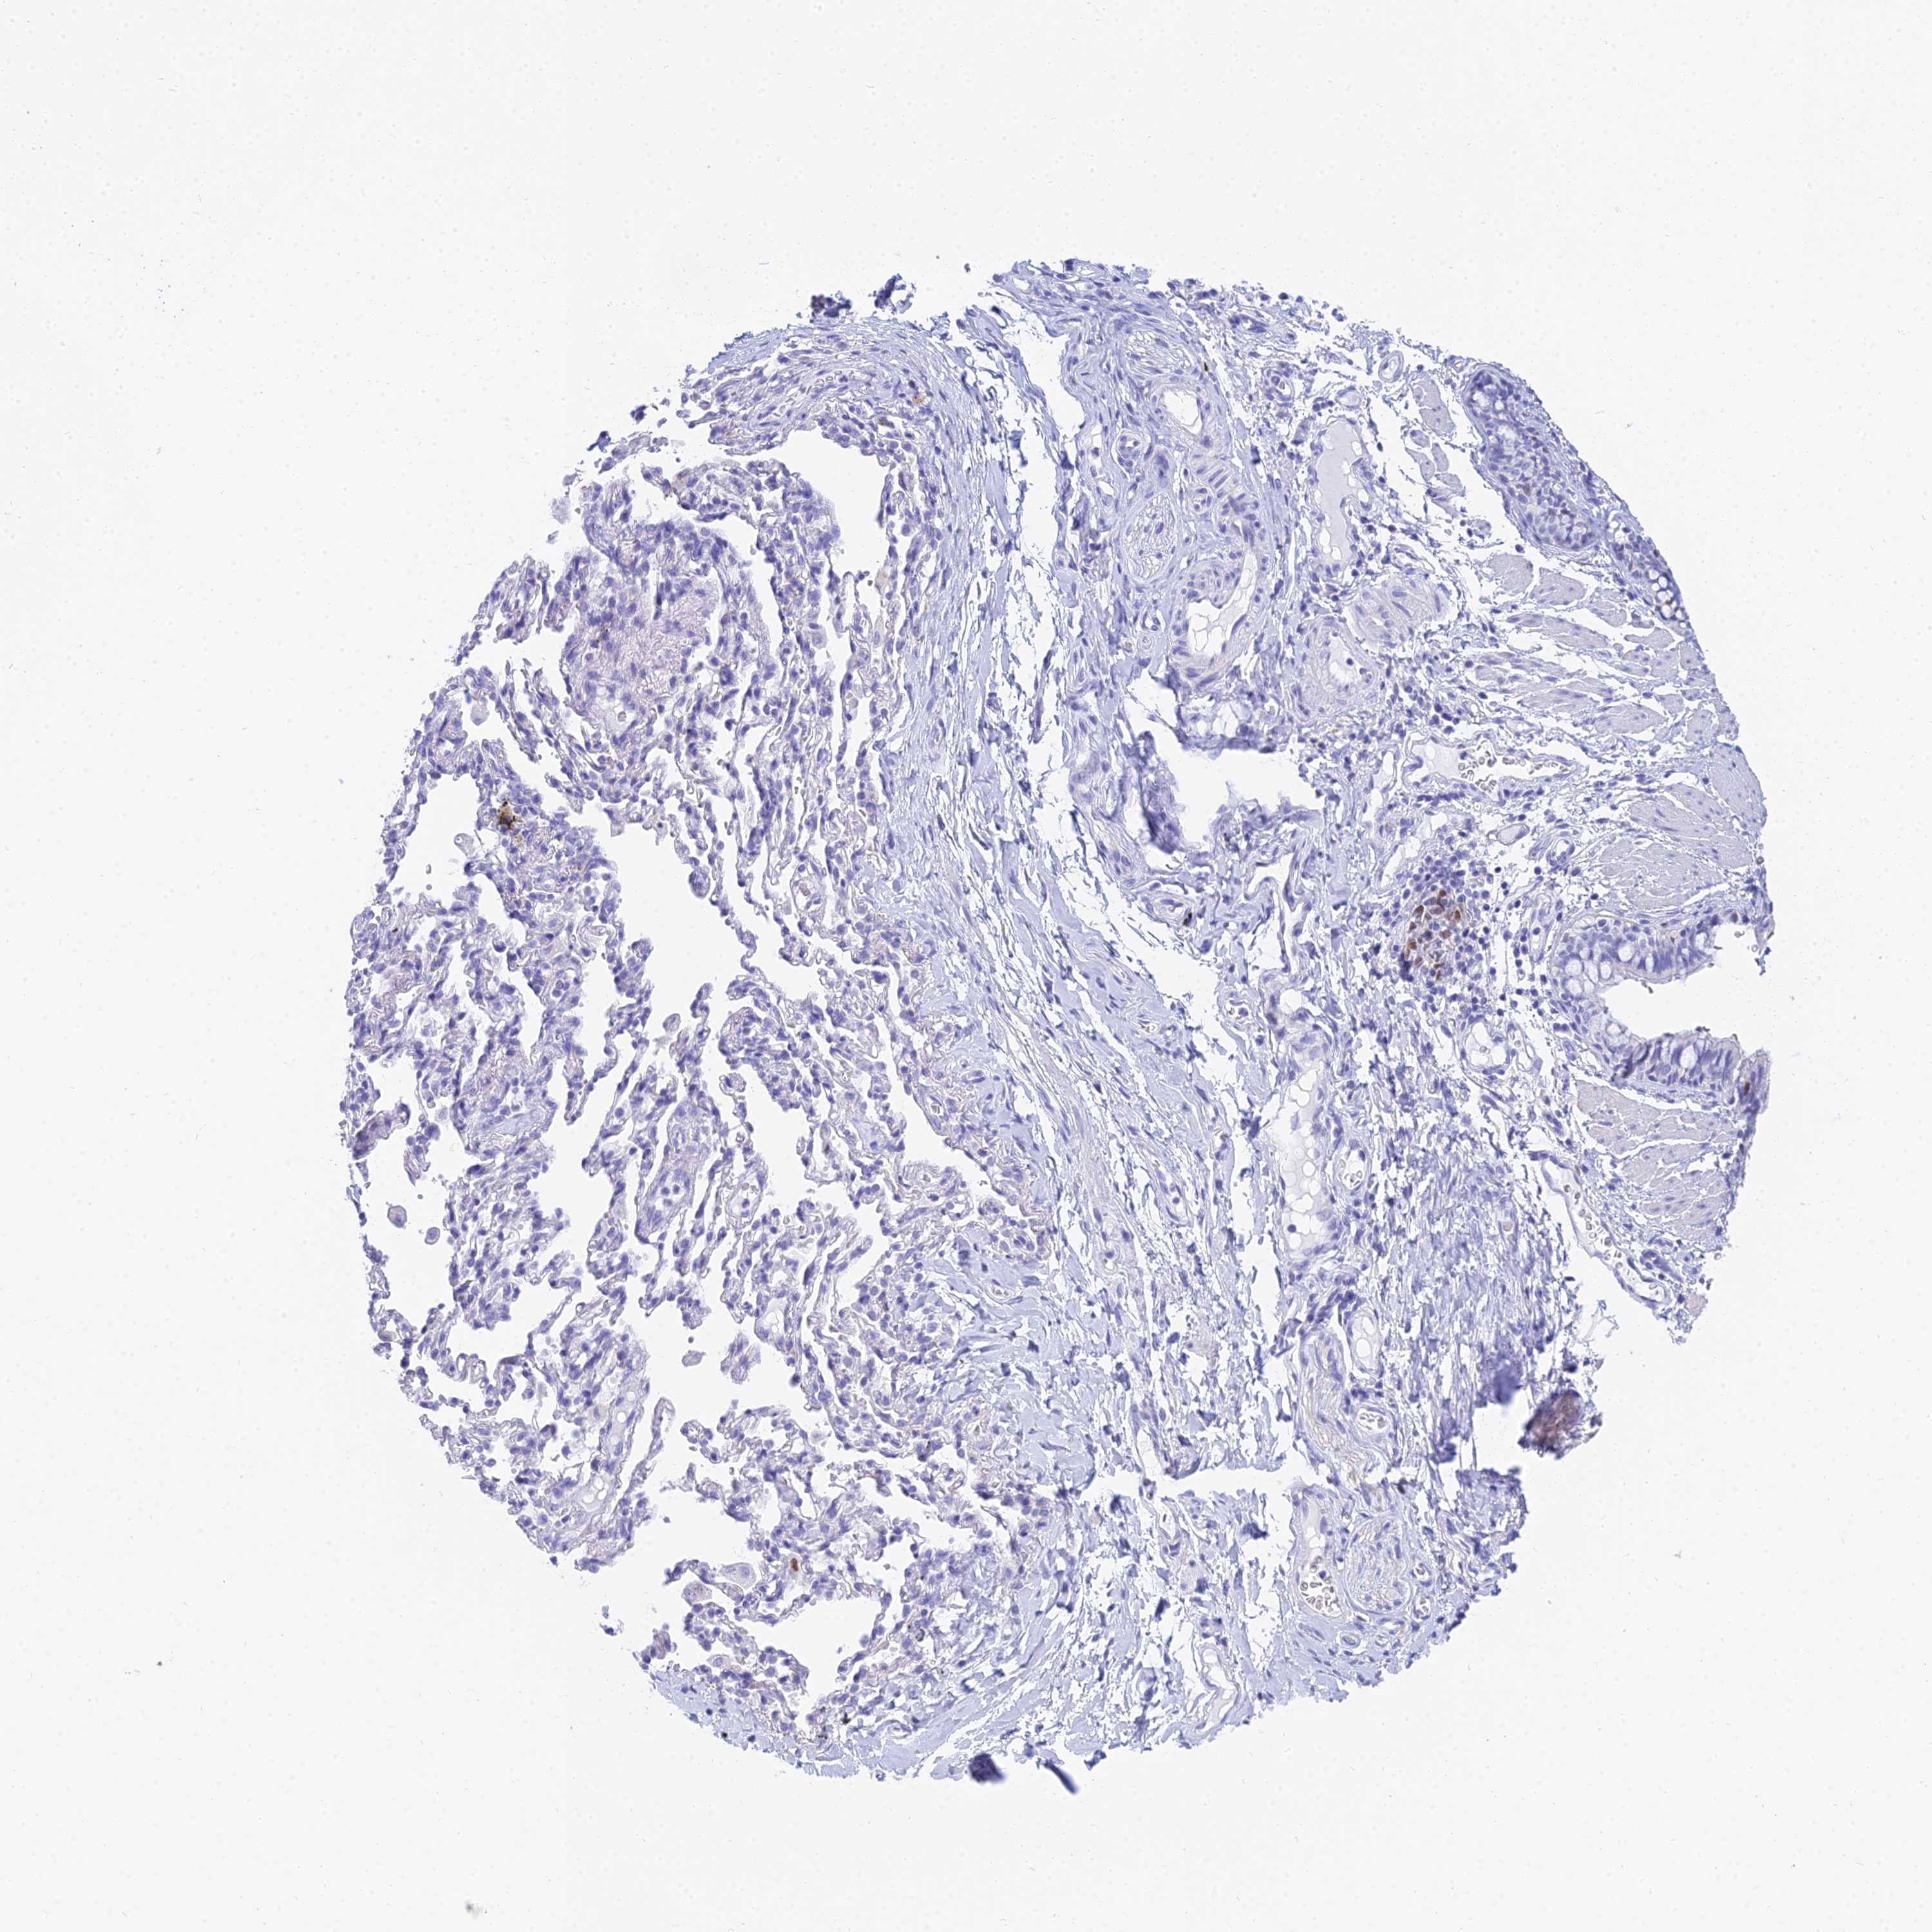

BRONCHUS